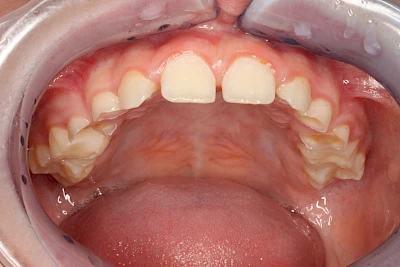

Über die Zeit können verschiedene Prozesse die Zahnhartsubstanzen aufzehren:

- Abnutzung durch Kauen (Abrasion) oder duch durch übermäßiges Knirschen bzw. Pressen (Attrition)

- Säurebedingte Auswaschung (Erosion)

- Knirschen bzw. Pressen und ungünstige Putztechnik (Druck): keilförmige Defekte